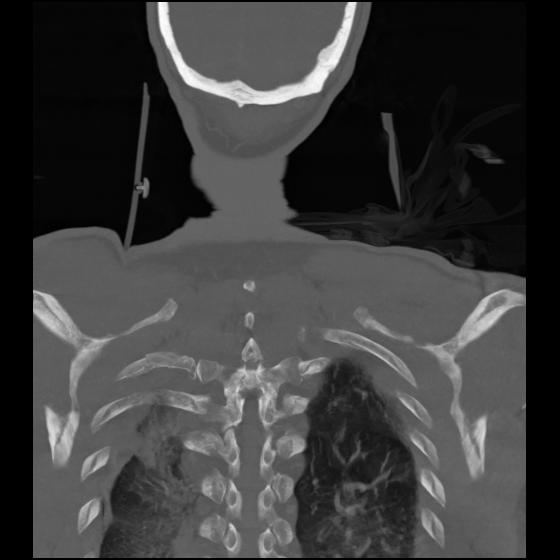

23 ANGIO,CE,Cor-MIP,5.000,ANGIO,Cor-MIP,